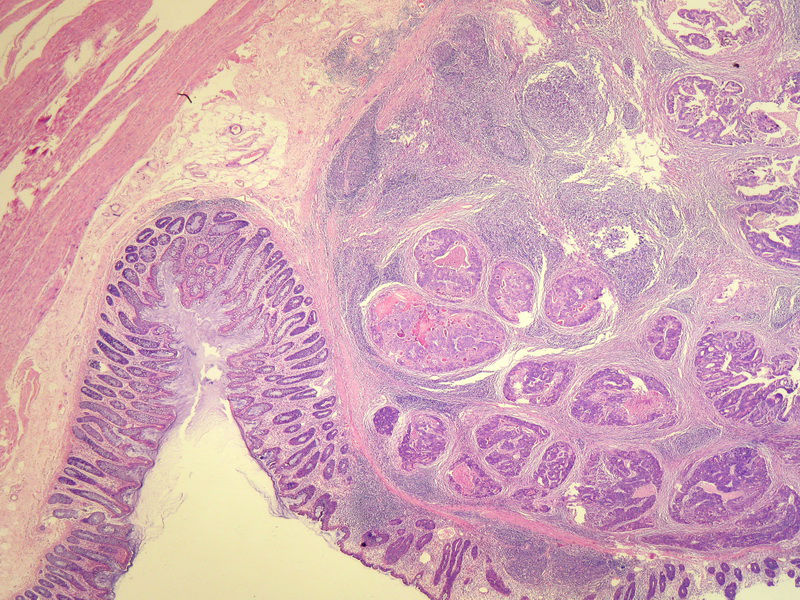

70岁男性,乙状结肠息肉样肿物。

请教:这个乙状结肠肿瘤侵犯到哪一层??图1

×参考诊断

粘膜下层

仅就浸润的深度而言,粘膜下层应该没什么争议。但是肿瘤表面的粘膜腺体是很好的,从低倍图看,不能排除是个转移灶的可能。请临床再查一查除了这个以外别的部位还有没有肿块。

浸润深度为粘膜下层,可粘膜表面的腺体完整,同意楼上的观点。谢谢